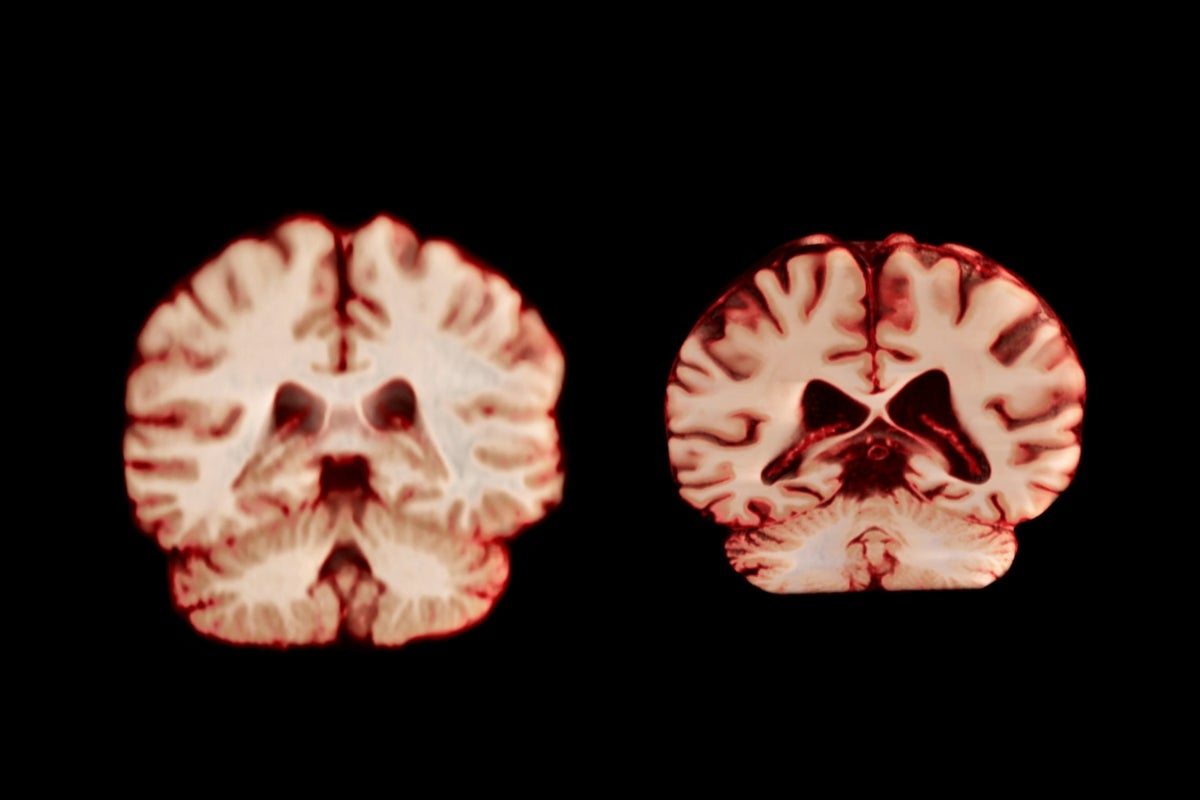

Riduzione del volume cerebrale

Si tratta di un processo graduale che inizia decenni prima e accelera dopo i settant’anni. La corteccia prefrontale, la regione che ci permette di pianificare, prendere decisioni complesse, controllare gli impulsi e mantenere l’attenzione sostenuta, è una delle aree più colpite. Anche la sostanza bianca, ovvero le fibre nervose avvolte nella mielina che collegano diverse regioni del cervello, subisce alterazioni. La mielina, lo strato protettivo che permette agli impulsi elettrici di viaggiare rapidamente tra i neuroni, inizia a deteriorarsi.